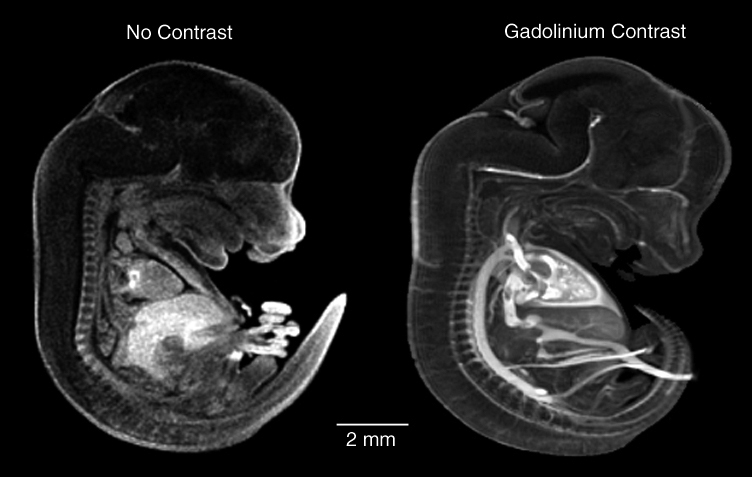

Magnetic Resonance Imaging

Mouse Embryo

Magnetic Resonance Imaging